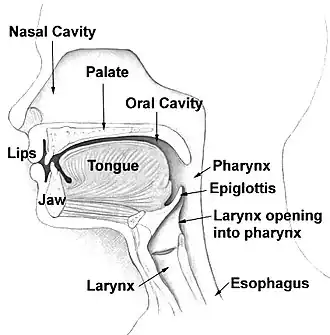

La faringe (gr. φάρυγξ pharynx) è il canale muscolo-membranoso del cavo orale che si connette con la cavità nasale, l'esofago, la laringe e l'orecchio medio.

La faringe è un organo presente sia nei vertebrati sia negli invertebrati, sebbene la struttura differisca a seconda della specie. Negli esseri umani la faringe è parte dell'apparato digerente e di quello respiratorio ed è importante per la fonazione.[1] La faringe umana è convenzionalmente divisa in tre sezioni: il rinofaringe (o nasofaringe), l'orofaringe e la laringofaringe (o ipofaringe), da non confondersi con la laringe, primo tratto delle vie respiratorie proprie.

La faringe costituisce la parte della gola situata immediatamente dietro la cavità nasale e orale, sopra l'esofago e la laringe e davanti alle vertebre cervicali (al livello del collo).

Nell'uomo la faringe è un canale muscolo-mucoso, impari e mediano del collo; ha la forma di un cono rovesciato, con l'apice rivolto inferiormente e la base superiormente. È lunga mediamente dai 12 ai 14 cm con una larghezza variabile principalmente in base al tono muscolare. Origina alla base del cranio, all'altezza delle coane con l'apertura superiore faringea costituendo la rinofaringe; scende poi all'altezza dell'istmo delle fauci nell'orofaringe, termina infine con la laringofaringe all'altezza di C6 dove si continua a pieno canale nell'esofago. La faringe rappresenta un importante crocevia anatomico e funzionale tra gli apparati digerente e respiratorio, considerato il passaggio sia del bolo sia dell'aria all'interno del canale faringeo. Presenta nel suo epitelio organi linfoidi che garantiscono difesa aspecifica contro eventuali agenti patogeni. Essa prende rapporto, dall'alto in basso, con le coane, il palato molle, l'ugola, l'istmo delle fauci, l'epiglottide, l'adito laringeo, la faccia posteriore delle cartilagini aritenoidi, la faccia posteriore della cartilagine cricoide e con i muscoli associati a queste strutture. La faccia posteriore è continua ed è in rapporto con lo spazio retrofaringeo e con la fascia cervicale profonda. Le pareti laterali si pongono in relazione con lo spazio faringomandibolare, in cui si trovano i fasci vascolo-nervosi del collo. Più inferiormente, le cartilagini cricoide e aritenoidi producono dei rilievi sulla superficie laterale della faringe, che producono due incavature, i recessi piriformi. Nel fondo di ciascun recesso è apprezzabile la piega del nervo laringeo superiore, che decorre caudalmente e medialmente.

La faringe viene convenzionalmente divisa in tre porzioni tra loro comunicanti: la rinofaringe, l'orofaringe e la laringofaringe.

Il rinofaringe è la parte superiore della faringe, il suo limite anteriore sono le coane, le due aperture posteriori della cavità nasale, separate dal setto nasale, mentre il suo limite postero-inferiore è l'istmo faringeo, uno spazio situato tra il margine posteriore del palato molle e la parete posteriore della rinofaringe, che la mette in comunicazione con l'orofaringe e tramite questa con la cavità orale. La volta della rinofaringe è concava e inclinata inferiormente, costituita dalla porzione posteriore del corpo dello sfenoide, è ricoperta da mucosa ed è occupata per buona parte dalla tonsilla faringea. La volta si continua inferiormente con la parete posteriore della rinofaringe, anch'essa leggermente concava e formata perlopiù dal muscolo costrittore superiore della faringe. Il pavimento della rinofaringe è costituito dalla superficie superiore del palato molle. Le pareti laterali della rinofaringe presentano su ciascun lato l'orifizio della tuba uditiva (o tromba di Eustachio), di forma triangolare, evidenziato superiormente e ai lati da una plica mucosa sporgente, il torus tubarius, che si origina a causa della presenza dell'estremità cartilagine formante la tuba uditiva che sporge all'interno della rinofaringe, ricoperta da mucosa. A partire dall'estremità posteriore del torus tubarius discende una plica mucosa, la piega salpingofaringea, che ricopre il muscolo salpingofaringeo; una seconda plica, la piega salpingopalatina, si estende dall'estremità antero-superiore del torus sino a livello dell'estremità posteriore del palato molle. Posteriormente all'orifizio della tuba uditiva giace la piccola tonsilla tubarica, superiormente si trova una depressione, la fossa sovratubarica, mentre posteriormente al torus tubarius si apre il piccolo recesso faringeo laterale (fossetta di Rosenmuller). La mucosa della rinofaringe è irrorata dal ramo faringeo dell'arteria mascellare interna e innervata dal ramo faringeo proveniente dal ganglio pterigopalatino; arteria e nervo decorrono entrambi nel canale palatovaginale. La rinofaringe presenta una porzione anteriore dove la mucosa è costituita da un epitelio ciliato pseudostratificato ricco di cellule caliciformi mucipare che sono intercalate tra una cellula e l'altra (epitelio respiratorio); tra le cellule si aprono anche gli orifizi dei canali delle minuscole ghiandole sierose, mucose o siero-mucose presenti nella mucosa e nella sottomucosa della rinofaringe. La porzione posteriore della rinofaringe è costituita da epitelio pavimentoso stratificato non cheratinizzato. Tra le due porzioni si distingue una piccola porzione intermedia che presenta cellule cilindriche provviste di microvilli apicali.

Orofaringe

L'orofaringe è la porzione intermedia della faringe. Il suo limite superiore è il palato molle e il suo limite inferiore è il margine superiore dell'epiglottide. È in comunicazione superiormente con la rinofaringe, inferiormente con la laringofaringe e anteriormente con la cavità orale attraverso l'istmo delle fauci delimitato lateralmente dagli archi palatoglossi. La volta dell'orofaringe non esiste nella porzione posteriore mentre anteriormente è costituita dalla superficie inferiore del palato molle. Il palato molle è una grossa piega mucosa collocata posteriormente al palato duro, diretta postero-inferiormente, di consistenza più morbida e dal colorito rossastro, più scuro rispetto al palato duro. La sua superficie superiore e quella inferiore sono ricoperte da mucosa, ma la superiore presenta un epitelio respiratorio, mentre l'inferiore un epitelio stratificato non cheratinizzato. Nella mucosa sono presenti numerose ghiandole che costituiscono buona parte dello spessore del palato molle, mentre più profondamente è collocata la componente muscolare; sono piuttosto frequenti aggregati linfoidi. Il terzo anteriore del palato molle è il meno mobile perché costituito prevalentemente dall'aponeurosi palatina che lo unisce al palato duro e non da muscoli; l'aponeurosi palatina è a sua volta costituita dal prolungamento dei tendini del muscolo tensore del velo palatino. L'estremità posteriore del palato molle discende inferiormente in un processo a forma di goccia chiamato ugola, anch'esso ricoperto da mucosa e costituito internamente dal piccolo muscolo dell'ugola. Le pareti laterali dell'orofaringe sono costituite dagli archi palatofaringei posteriormente e dagli archi palatoglossi anteriormente. Gli archi palatoglossi originano dal palato molle e scendono inferiormente e anteriormente sino alla radice della lingua, contengono il muscolo palatoglosso mentre gli archi palatofaringei decorrono dalla porzione posteriore del palato molle alla parete della faringe e contengono il muscolo palatofaringeo. Tra i due archi ipsilaterali si viene a formare una nicchia, la fossa tonsillare, in cui è accolta la tonsilla palatina. La parete posteriore dell'orofaringe si continua superiormente con quella della rinofaringe ed è a livello di C2-C3. Le arterie che irrorano il palato molle sono un ramo palatino dell'arteria faciale e un ramo dell'arteria faringea ascendente, le vene invece drenano nel plesso pterigoideo. Il palato molle è innervato dal nervo palatino minore, mentre le pareti dell'orofaringe da rami del nervo glossofaringeo che trasportano informazioni riguardanti la sensibilità generale. Il nervo palatino minore trasporta anche la sensibilità gustativa derivante dai calici gustativi non collocati sulla superficie della lingua.

Laringofaringe

La laringofaringe è la porzione inferiore della faringe. Il suo limite superiore è il margine superiore dell'epiglottide, il suo limite inferiore è il margine inferiore della cartilagine cricoidea, all'altezza del margine inferiore della sesta vertebra cervicale per poi continuare inferiormente nell'esofago. La parete posteriore della laringofaringe si continua con quella dell'orofaringe superiormente e dell'esofago inferiormente. La parete anteriore della porzione superiore della laringofaringe è idealmente l'adito laringeo, cioè la cavità d'ingresso per la laringe che poi decorre anteriormente alla laringofaringe. L'adito laringeo è delimitato superiormente e anteriormente dalla superficie inferiore dell'epiglottide. Lateralmente all'adito laringeo vi sono i due recessi piriformi che sono limitati medialmente dalla piega ariepiglottica e lateralmente dai margini della cartilagine tiroidea.